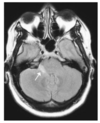

There is a mass in the left hemisphere (A) surrounded by an extensive area of low density (B) which represents oedema. There is midline shift (C) and compartmental hydrocephalus (demonstrated by the enlarged lateral ventricles on the right (D) due to compression of the ventricular system at the foramen of Monro. There is herniation of the uncus of the left temporal lobe seen on the lower slice (E).

DWI MRI can be used to differentiate cystic/necrotic tumour from an abscess.

DWI indicates the degree to which water molecules can diffuse out of cells.

It is typically restricted in abscesses, yielding hyperintense signal on DWI. Tends not to be restricted in tumours.

The pattern on the apperent diffusion coefficient sequence is the opposite.

Abscess ring may appear hypointense on DWI a feature not seen in tumours.